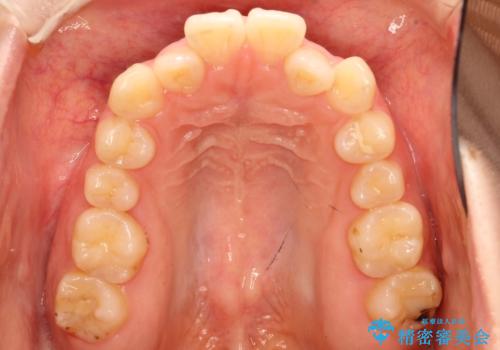

前歯にがたつきがあり、上下の歯が咬み合っていない状態でした。

歯列の横幅をひろげるのと、歯と歯の間をわずかに削ることにより、前歯のがたつきと、開咬を改善しました。